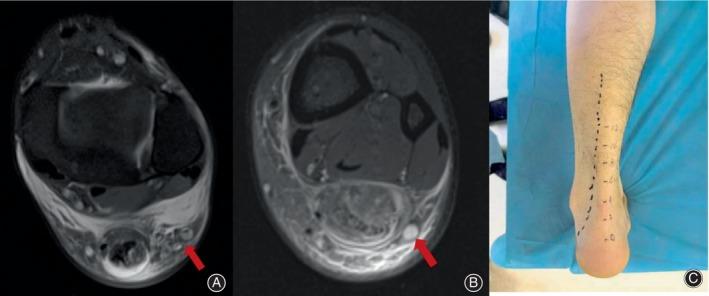

Percutaneous repair is an alternative to open surgical repair of the Achilles tendon with comparable, functional results and low re-rupture and infection rates; however, sural nerve injury is a known complication. The purpose of this study is to design a new surgical procedure, the minimally invasive peritendinous submembrane access technique (MIS-PSAT). It offers optimal results, with excellent functional outcomes, and with minimal soft tissue complications and sural nerve injury.

The MIS-PSAT for acute Achilles tendon rupture is easy to perform with few complications. Importantly, the surgical technique reduces the risk of sural nerve injuries. Patients have high postoperative satisfaction, low re-rupture rates, and muscle strength, and endurance can be restored to levels similar to those on the healthy side.